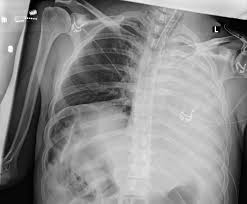

They did a cat scan and said the nod was.08 or 08 centimeters in dia. Here's why cancer can look like an infection: Pneumonia is a common lung infection. Note the increased soft tissue opacity in the lungs that partially obscures blood vessel margins. Malignant tumors trigger inflammation in surrounding normal lung tissue, and they may obstruct. Your veterinarian may recommend an fna and cytology or a biopsy, to confirm the diagnosis, and determine exactly what kind of lung cancer is present. Lung cancer develops due to the overgrowth of. You can see on the left of the image a dark (relatively clear) lung.

Dog pneumonia or lung cancer. Lung cancer develops due to the overgrowth of. Everybody still looks at lung cancer as a smoker's disease, but i never smoked. They won't say i have lung cancer but they need to do this pet sacn to rule it out. Lung cancer is actually the number one killer when it comes to cancers. You can see on the left of the image a dark (relatively clear) lung. They did a cat scan and said the nod was.08 or 08 centimeters in dia. Primary lung cancer are frequently located in the caudal (towards the hind end of the pet) lung lobes, however can be located in any lung lobe and are usually a single mass in the lungs, unless the tumor has spread. Pneumonia in people with lung cancer. Lung cancer can predispose one to pneumonia but in that case the pneumonia would recur in the same place in your lung each time. This is not to say the effects on a loved dog's body are the same as an infection. Note the increased soft tissue opacity in the lungs that partially obscures blood vessel margins. A definitive diagnosis of lung cancer requires a sample of tissue (biopsy).